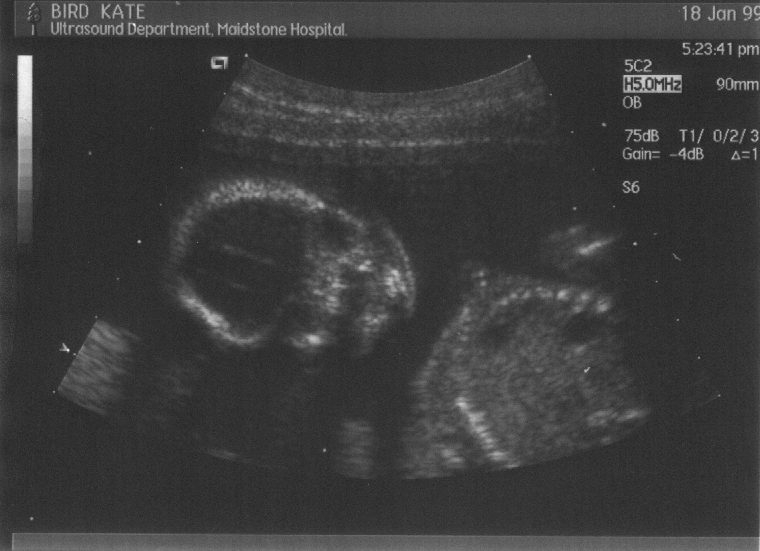

Pictures from the 37–week (& 6 days) stage in the Fœtal Assessment Unit. Check ’em out:

These are the six scans taken at the week–20 “abnormality scan”. Click on the thumbnail to view the full picture :-

Week 20, scan 1  (bust, side–on)

Week 20, scan 2  (front ‘face’ view)